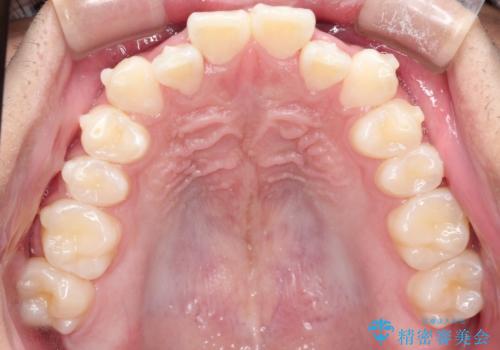

- 前歯のがたつきを主訴に来院されました。

上顎の前から2番目の歯の噛み合わせが反対になっていました。

抜歯矯正も考えられるケースでしたが、非抜歯での矯正を希望され、インビザラインにて治療することとなりました。